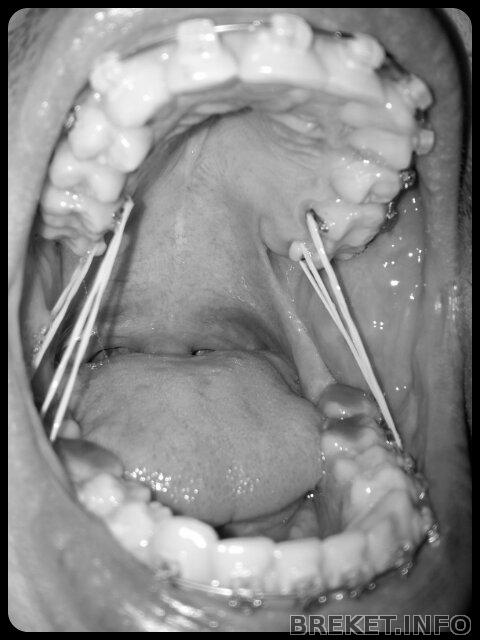

Был вчера на очередном приёме у ортодонта. Установили ещё пару кнопок, на внутреннюю сторону зубов(для тяг). Врач спрашивала как часто я носил тяги до этого, я сказал что не так часто как хотелось бы. В итоге, она мне пригрозила становить нёбный расширитель, если я не стану носить тяги постоянно. Вот теперь уже сутки не снимаю два пары тяг, зубы болят так, словно мне первый день брекеты установили... ((

Спросил, на счёт того, не нужна ли мне проф. чистка(например air flow). Так как зубы я чищу не так как предписывали - каждый раз после еды, а только два раза в день, порой только один. Но мне сказали, что всё хорошо, налёта нет и чистка не требуется. Ну хоть что-то приятное сказали))